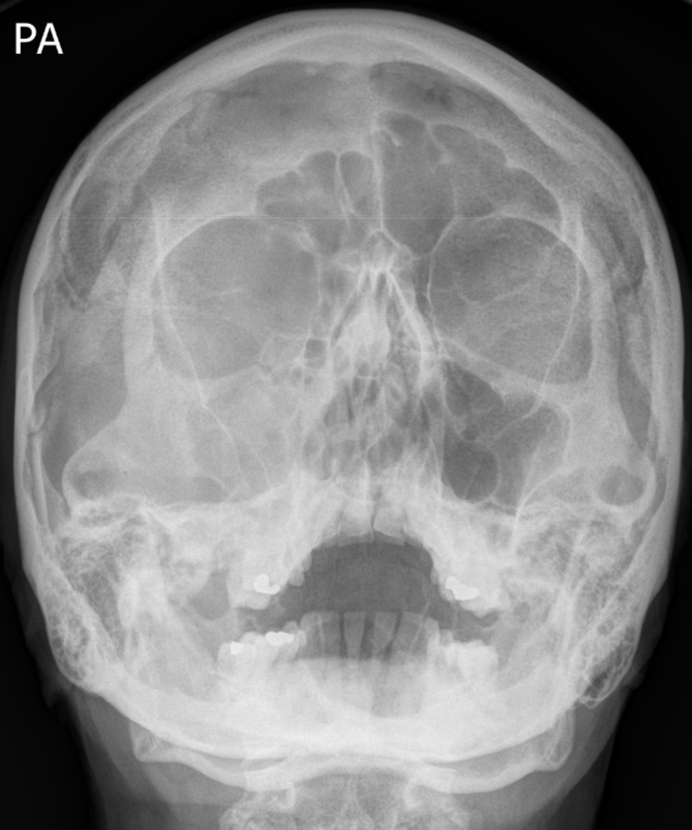

Right zygomaticomaxillary complex (ZMC) fracture